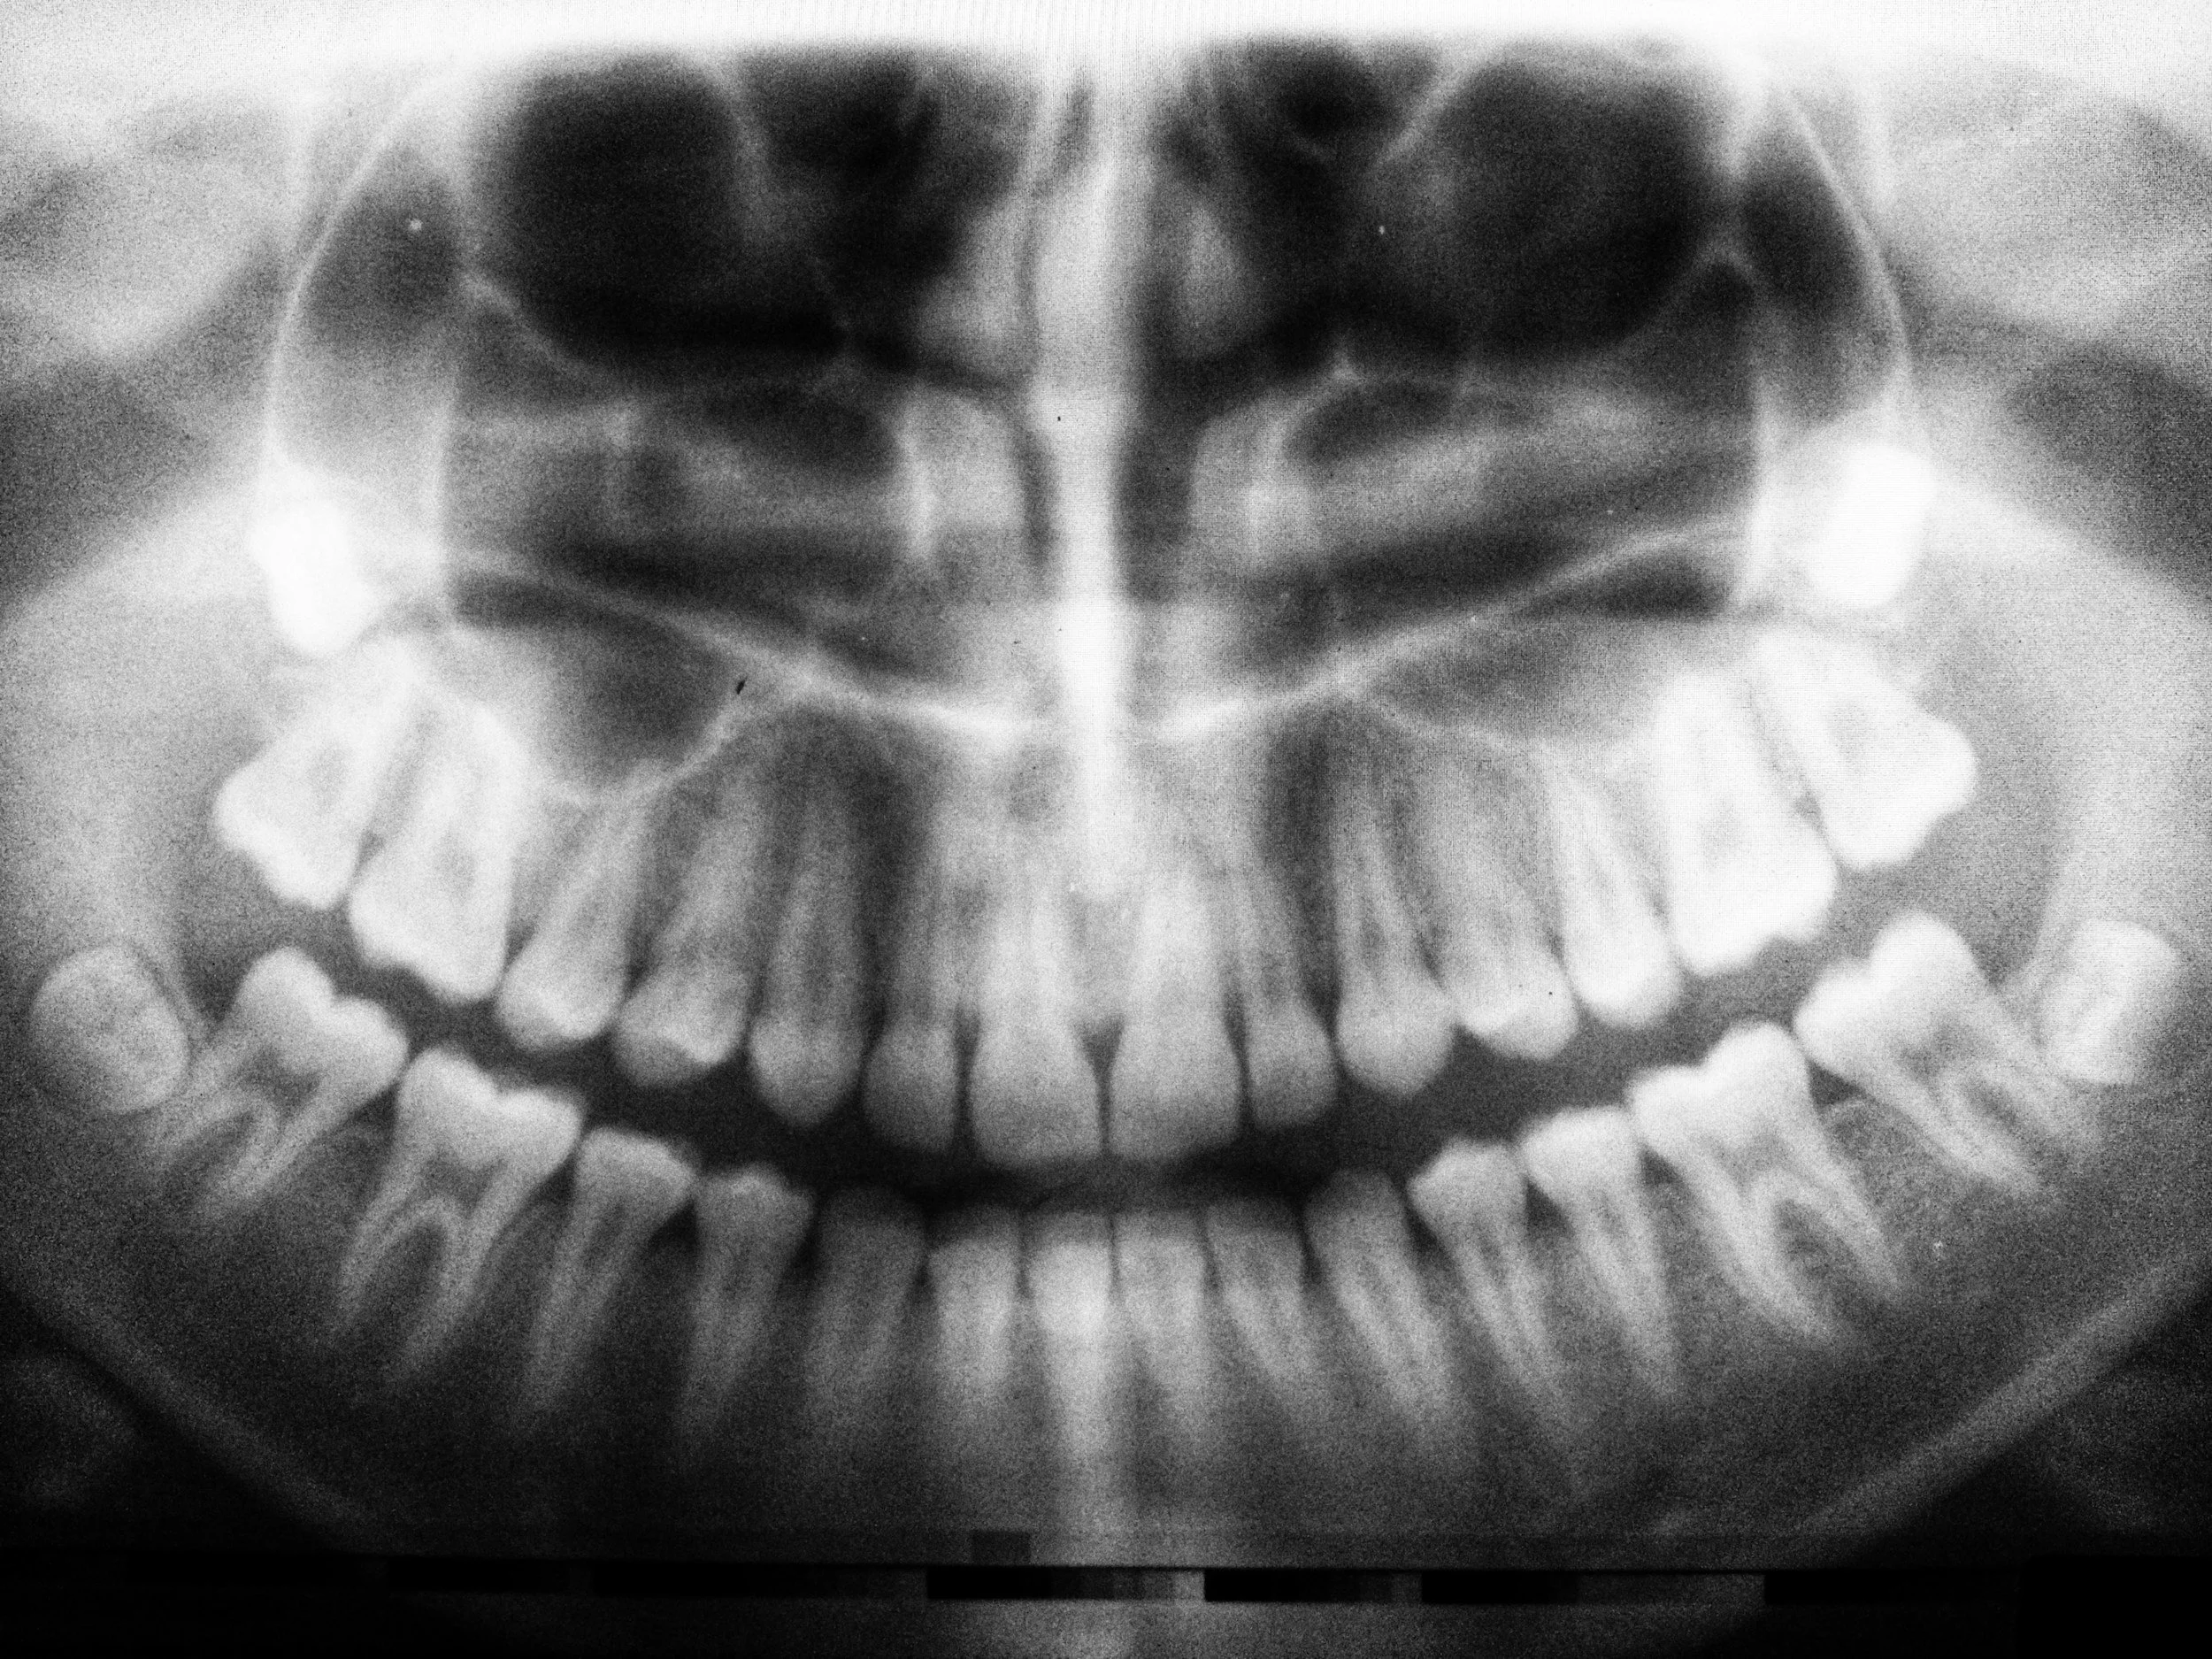

Digital X-Rays

Digital x-rays are safe, quick, and comfortable. Using the latest technology, we can create high-resolution images of your mouth’s structure, so we can make accurate diagnoses and treatment plans. Digital x-rays use only a fraction of the radiation as traditional film x-rays, so you can rest easy. X-rays help detect cavities, gum disease, bone loss, infection and many other conditions. The routine visits allow us to take the x-rays needed to prevent early tooth loss and other serious issues in the mouth.